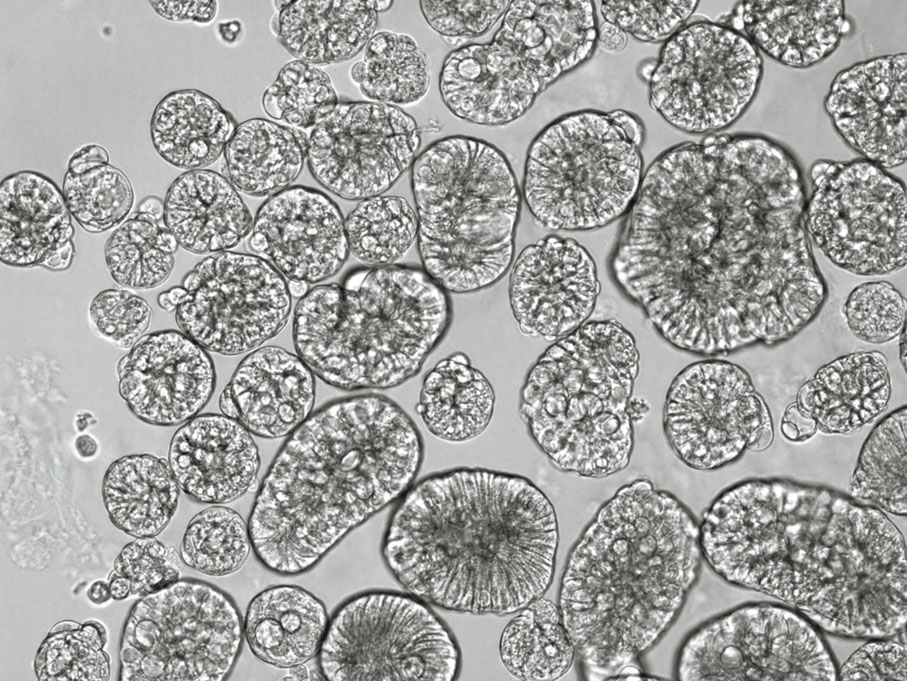

所謂類器官,就是類似於人體器官的模型,透過成體幹細胞培養,「只需要大約0.5cm的肺組織,就可以建立起一個類器官,可以在體外不斷增殖、放大、連續培養……再透過分化培養之後,就可以完全模擬人類的呼吸道上皮」,周婕舉例,人體呼吸道的杯狀細胞會分泌黏液,將病毒黏附,再透過纖毛細胞擺動,將分泌黏液往上排,直到咽喉部再變成痰,這是呼吸道的一個重要生理防禦功能。

「我們的類器官就可完全模擬呼吸道的這種細胞組成、形態與功能……而且當我們為你建立一個類器官,它會保留你身體的DNA,你的一些細胞特點、功能,是個性化的」,周婕續解釋,每個人受新冠病毒感染的風險都不同,其中一個決定因素,在於他們各自的呼吸道上皮細胞,對病毒的易感性,「若為人們各自建立起類器官,就可以代表他們各自的易感性。」